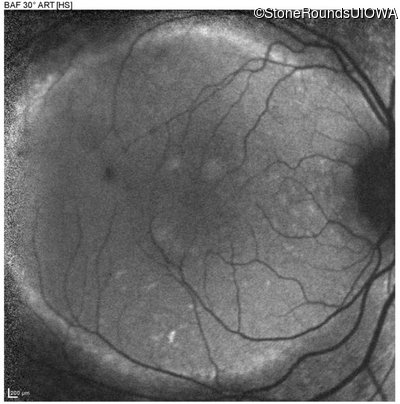

The clinical features supporting the diagnosis of the enhanced S-cone syndrome (ESCS) in this patient include: stable night blindness since at least the second year of life, normally sighted parents, nummular pigment in the mid-periphery of the fundus that stops abruptly at the temporal arcades and disorganization of the retinal layers (seen on OCT) anterior to the temporal arcades.